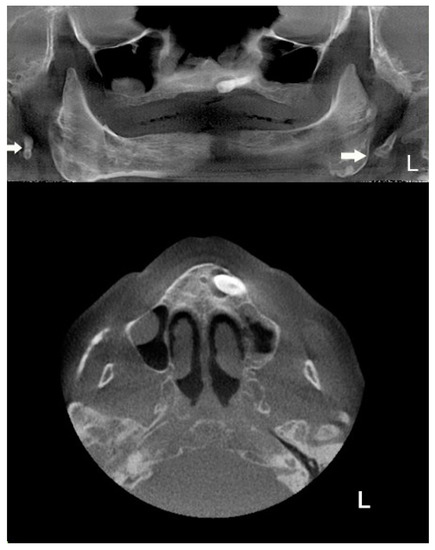

Patient #2′s panoramic X-ray acquisition showed bilaterally pathological nodular elongation of the left and right styloid processes extending beyond the lower border of the mandible (Figure 3); an unerupted impacted maxillary left canine and, on the right side, the sinus mucocele was also observed. A tentative diagnosis was made that the patient had true Eagle’s syndrome due to the unusual panoramic image and pain experiences.

The extracted CBCT’s panoramic view shows an atypical bilateral elongation of the styloid process, with the unerupted impacted maxillary left canine and, on the right side, the sinus mucocele; the CBCT’s extracted panoramic and axial views of the maxilla shows a more detailed unerupted impacted maxillary left canine and two additional sinus pathologies in the maxillary sinuses; in the left maxillary sinus, there was chronic inflammatory hyperplastic mucosa, while the right maxillary sinus exhibited a sinus mucocele (Figure 4).

Figure 3. Panoramic X-ray acquisition showing bilaterally pathological nodular elongation of the left and right styloid processes extending beyond the lower border of the mandible; an unerupted impacted maxillary left canine and, on the right side, the sinus mucocele can also be seen.

Figure 4. The axial cone beam computed tomography (CBCT) slice shows (upper image): panoramic radiography showing an unerupted maxillary left canine with a cyst-like formation around the canine crown and sinus pathology in the right maxillary sinuses. Elongated bilateral stylohyoid complex (SHC) processes are present and attain over one third of the mandibular ramus length (white arrows); (lower image): CBCT reconstruction images showing chronic inflammatory hyperplastic mucosa in the left maxillary sinus, impacted canine, while the right maxillary sinus exhibits a mucocele affecting the latero-basal portion of the sinus.